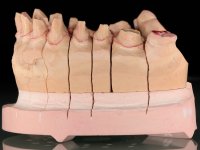

Foi proposto ao paciente fazer uma reabilitação total com infraestruturas em zircónia revestidas a cerâmica. No maxilar superior, seriam realizadas 6 coroas (1.3/1.2/1.1/2.1/2.2/2.3), uma ponte de 3 elementos (1.4/1.5/1.6) e uma ponte de 4 elementos (2.4/2.5/2.6 e 2.7). No maxilar inferior, foram propostas 7 coroas (4.3/4.2/4.1/3.1/3.2/3.5 /3.6) e duas pontes (4.4//4.5/4.6) e (3.3/3.4#/3.4).O objetivo seria subir a D.V.O., descruzar a mordida do lado direito, eliminar as infiltrações e as exposições radiculares e reabilitar o paciente com estruturas protéticas com aspeto mais natural.

Avaliada a situação inicial em conjunto com o médico dentista, foi considerado prioritário alterar a forma dos dentes, subir 1.5mm a D.V.O. e descruzar a mordida do 1º Quadrante. Na confeção da ponte provisória superior de acrílico com reforço metálico foram já ensaiadas essas alterações. Optamos por um monobloco de 13 dentes com o intuito de manter a estabilidade posicional dos dentes re- preparados. Após remoção das coroas e pontes antigas foi feita a re-preparação dentária. A ponte provisória foi rebasada em boca, primeiro com acrílico auto-polimerizável e depois com resina composta. Após 4 semanas de integração da ponte provisória superior foi confecionada a ponte provisória inferior, corrigindo-se finalmente as discrepâncias existentes no plano oclusal. As impressões foram realizadas com a técnica de dupla mistura, com dupla mistura. Simultaneamente foram feitos os registos da relação inter-maxilar e da relação do maxilar superior com a base do crânio, utilizando o arco facial. Montados os modelos de trabalho em articulador semi-ajustável, foram confecionadas as peças próteticas, utilizando tecnologia CAD-CAM para a realização das infra-estruturas em zircónia. A colocação da cerâmica foi feita procurando que a forma dos dentes reproduzisse uma forma anatómica natural. A tonalidade foi condicionada pela vontade do paciente. Foi feita uma prova com a cerâmica em “biscuit” para verificação técnica e validação estética. Após aprovação pelo paciente o trabalho foi finalizado e colocado em boca.